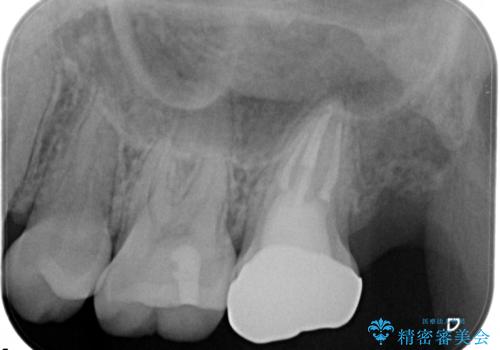

- 他院にて奥歯の治療をしても痛みが引かずに、ラバーダムの存在を知り、無菌的な治療を行える病院を探して当院を受診されました。

根管治療~フルジルコニアクラウンにて修復しております。

治療前には打診、圧痛がありましたが治療後には症状が消失し、3ヶ月後のレントゲンでも透過像の縮小を認めています。

治療介入時、根管内部にはカリエスや異物が存在する状態でしたが適切な処置を行うことで症状を改善することができました。